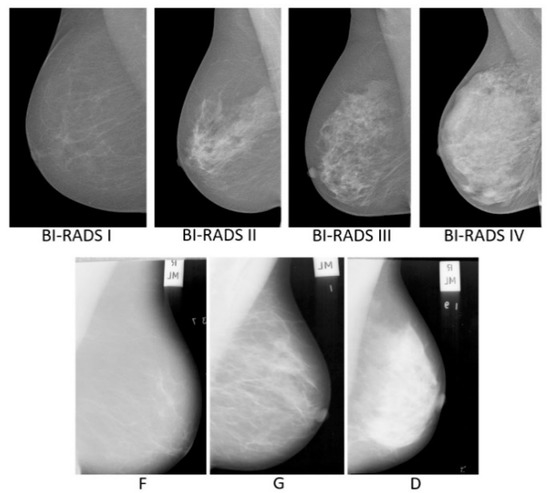

2. Materials

| Methods | Image Used | Results Evaluation Method | Results CA (%) | Density Categories |

| Intensity-based features + SVM [11] | 322 | Leave-one-image-out | 85.7 | 3 (F, G, D) |

| Intensity-based features + KNN [11] | 322 | Leave-one-image-out | 78.6 | 3 (F, G, D) |

| Intensity-based features + SVM [11] | 322 | Leave-one-woman-out | 77.0 | 3 (F, G, D) |

| Intensity-based features + KNN [11] | 322 | Leave-one-woman-out | 76.4 | 3 (F, G, D) |

| GLCM + KNN [6] | 322 | Leave-one-image-out | 82.0 | 3 (F, G, D) |

| LQP + SVM [25] | 322 | 10-fold cross validation | 86.13 | 4 (BI-RADS) |

| LBP + Bayesian Network [21] | 321 | 10-fold cross validation | 69.4 ± 0.92 | 3 (F, G, D) |

| ELBP + Bayesian Network [21] | 321 | 10-fold cross validation | 75.4 ± 1.05 | 3 (F, G, D) |

| u-ELBP + Bayesian Network [21] | 321 | 10-fold cross validation | 73.3 ± 0.64 | 3 (F, G, D) |

| M-ELBP + Bayesian Network [21] | 321 | 10-fold cross validation | 77.4 ± 1.06 | 3 (F, G, D) |

| LDP + Bayesian Network [21] | 321 | 10-fold cross validation | 76.0 ± 0.96 | 3 (F, G, D) |

| RIU2-LBP + SVM [26] | 322 | 5-fold cross validation | 73.8 ± 10.6 | 4 (BI-RADS) |

| RIU2-LTP + SVM [26] | 322 | 5-fold cross validation | 81.0 ± 9.5 | 4 (BI-RADS) |

| RIU2-LQP + SVM [26] | 322 | 5-fold cross validation | 82.1 ± 7.1 | 4 (BI-RADS) |

| RIU2-LSP + SVM [26] | 322 | 5-fold cross validation | 83.3 ± 8.8 | 4 (BI-RADS) |

| RIU4-LQP-HK + SVM | 322 | Leave-one-woman-out | 86.96 | 3 (F, G, D) |

| RIU4-LQP-HK + SVM | 322 | Leave-one-image-out | 93.21 | 3 (F, G, D) |

| RIU4-LQP-HK + SVM | 322 | 10-fold cross validation | 90.61 ± 4.78 | 3 (F, G, D) |

| RIU4-LQP-HK + SVM | 322 | 5-fold cross validation | 86.25 ± 5.24 | 3 (F, G, D) |